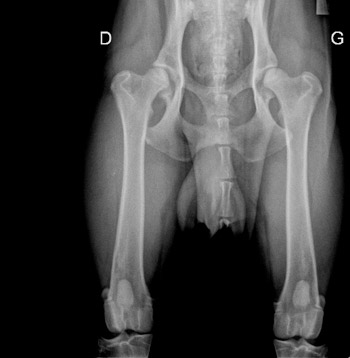

La dysplasie de la hanche (HD)

La dysplasie de la hanche est un fléau dans la plupart des races canines. Elle est décrite dès 1935 mais ne retient l'attention des éleveurs américains que dans la deuxième moitié de ce siècle.

La dysplasie est un terme générique qui concerne toutes les situations de défaut de coaptation des surfaces articulaires et qui se définit comme une affection héréditaire. Ce défaut est l'expression d'une laxité anormale de la tête fémorale dans la cavité acétabulaire. Elle peut être uni ou bilatérale. Elle est d'origine génétique mais avec une héritabilité moyenne, l'environnement jouant un rôle non négligeable.

La laxité articulaire n'est pas synonyme d'arthrose et tous les chiens dysplasiques ne développent pas une arthrose.

Le Lecteur Officiel, choisi par le Club, est chargé de porter un diagnostic de dysplasie ou de non-dysplasie sur les radios de dépistage à partir de 12 mois.

Les diagnostics sont classés selon plusieurs stades :

- Stade A (normal) : aucun signe de dysplasie

- Stade B (presque normal) : quelques imperfections

- Stade C (acceptable) : dysplasie légère

- Stade D : dysplasie moyenne

- Stade E : dysplasie grave

La lecture des radios des hanches stade A, B ou C est obligatoire pour obtenir une cotation 2, 3 ou 4. Pour l'homologation des Titres de Champions de France, seuls les stades A et B sont acceptés.

Les stades D et E n'obtiennent pas le Label HD.